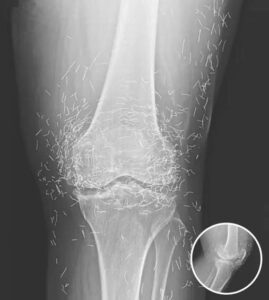

A 65-year-old woman in South Korea experienced a shocking medical discovery when doctors found hundreds of tiny gold needles embedded in her knee tissue during a routine X-ray. She had been suffering from chronic osteoarthritis, a condition that causes joint pain, stiffness, and inflammation due to cartilage breakdown.

In this case, the needles were intentionally left in her body as part of a long-term treatment strategy. Some practitioners believe that leaving gold needles or threads in place can provide ongoing stimulation to the affected area. However, medical professionals warn that this approach carries significant risks.

Dr. Ali Guermazi, a radiology expert from Boston University not involved in the case, explained that the human body can react negatively to foreign objects. Inflammatory responses, tissue damage, and infections are potential complications. Additionally, the embedded needles can interfere with medical imaging, making diagnosis more difficult.